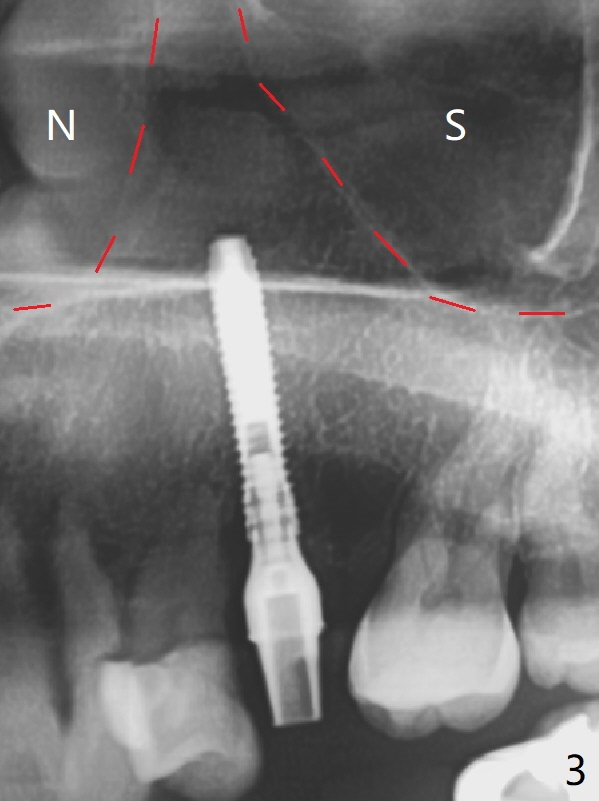

When a 2x16 mm parallel pin is inserted at #13 after extraction, PA does not show the upper end, as related to the long bone (Fig.1). In spite of underprep osteotomy, a 3.8x18 mm implant achieves ~ 20 Ncm of insertion torque (Fig.2). The long implant is still in the lower half of the triangular (cone-shaped) bone (Fig.3 red dashed line) between the nasal cavity (N) and the maxillary sinus (S). The bone is also wide. When a 4.5x5(5) mm abutment is placed, it is buccal. It appears that an angled abutment is needed for final restoration (probably 4.5x15 or 25 degrees, 5 mm cuff). When an angled abutment is placed 1 month posotp, the implant is found unstable. A healing abutment is placed (5.5x7 mm). Progressive loading is initiated 4-5 months postop. The implant becomes stable nearly 5 months postop (Fig.4), but the buccal gingiva is erythematous and tender, probably due to infected bone graft (one large piece), which is removed. One week later, the gingiva looks normal; impression is taken (Fig.5).